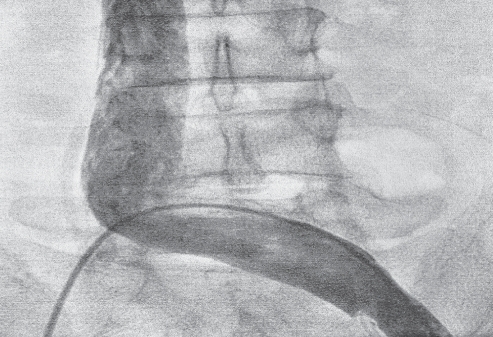

Evaluation at Nizam’s Institute of Medical Sciences revealed an unchanged chest x-ray and absence of new infiltrates on a computed tomography scan. Repeat Doppler examination revealed resolution of the left femoral vein, left iliac vein and IVC thrombi. This was confirmed by conventional venogram (Figure 1). A subsequent transesophageal echocardiogram (TEE) revealed a small freely mobile mass at the IVC-right atrium (IVC-RA) junction (Figure 2 and Video). The primary diagnostic consideration at this point was a residual adherent thrombus on the eustachian valve. Therapeutic alternatives included repeat systemic thrombolysis, local catheter-directed thrombolysis, surgical removal or continuation of anticoagulation. Given the risks of repeat thrombolysis, it was preferred to manage the patient conservatively with anticoagulation alone. However, the patient continued to have progressive worsening of dyspnea and hypoxia along with distinct episodes of pleuritic chest pain presumed to be due to recurrent pulmonary embolism. This prompted the decision to proceed with surgery after an in-depth discussion with the patient, his family and the cardiac surgeon. A preoperative coronary angiogram was normal. The patient duly underwent open heart surgery on cardiopulmonary bypass and a reddish-white mass (1 cm × 1.5 cm) attached to the IVC-RA junction was excised. There was no atrial septal defect or patent foramen ovale. Histopathology was consistent with layered thrombus attached to valve tissue (dense plate of collagenous fibrous tissue covered by endocardium). Postoperatively, the patient improved rapidly and returned to baseline functional status within two weeks. At six months follow-up, he remains asymptomatic and continues to be on warfarin.

Figure 1).

Conventional venogram showing no residual left iliac or inferior vena cava thrombus